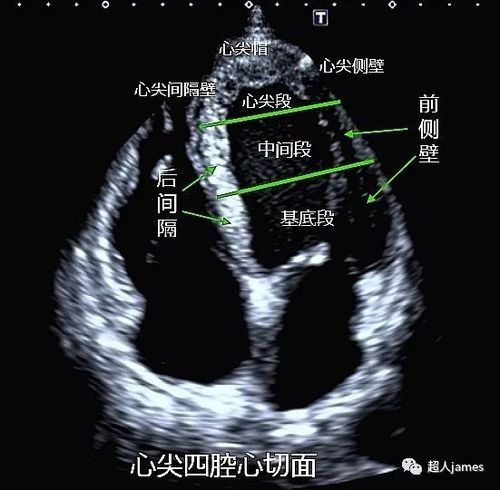

心尖四腔心切面示意图

心尖四腔心切面示意图,心尖五腔心切面示意图

心尖四腔心切面:前侧壁基底段,前侧壁中间段,后间隔基底段,后间隔

心尖四腔心切面(上)